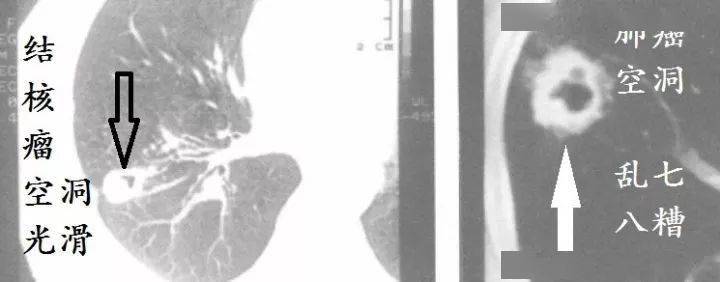

63088afe8b5749a49ba68d5b8bece586.jpeg

图4~图5 肺部CT

看吧,肺癌就是乱七八糟。

因为:鳞癌最容易烂掉!鳞癌天生的烂!乱七八糟的空洞,肿瘤内液化坏死,等等,大部分是鳞癌!